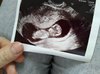

A oto moje maleństwo. <3

Wreszcie wczoraj na wizycie byłam. Bałam się jak diabli kiedy pani doktor robiła usg, bałam się o pracę serducha - sama nie wiem czemu - ale jak już usłyszałam to ojej.. nerwy wreszcie puściły i aż ręce trząść mi się zaczęły. Taka ulga że szok, i fascynacja że wreszcie po 11 tygodniach widzę moje szczęście.

Wszystko z nami dobrze!

Cieszę się jak cholera. :D